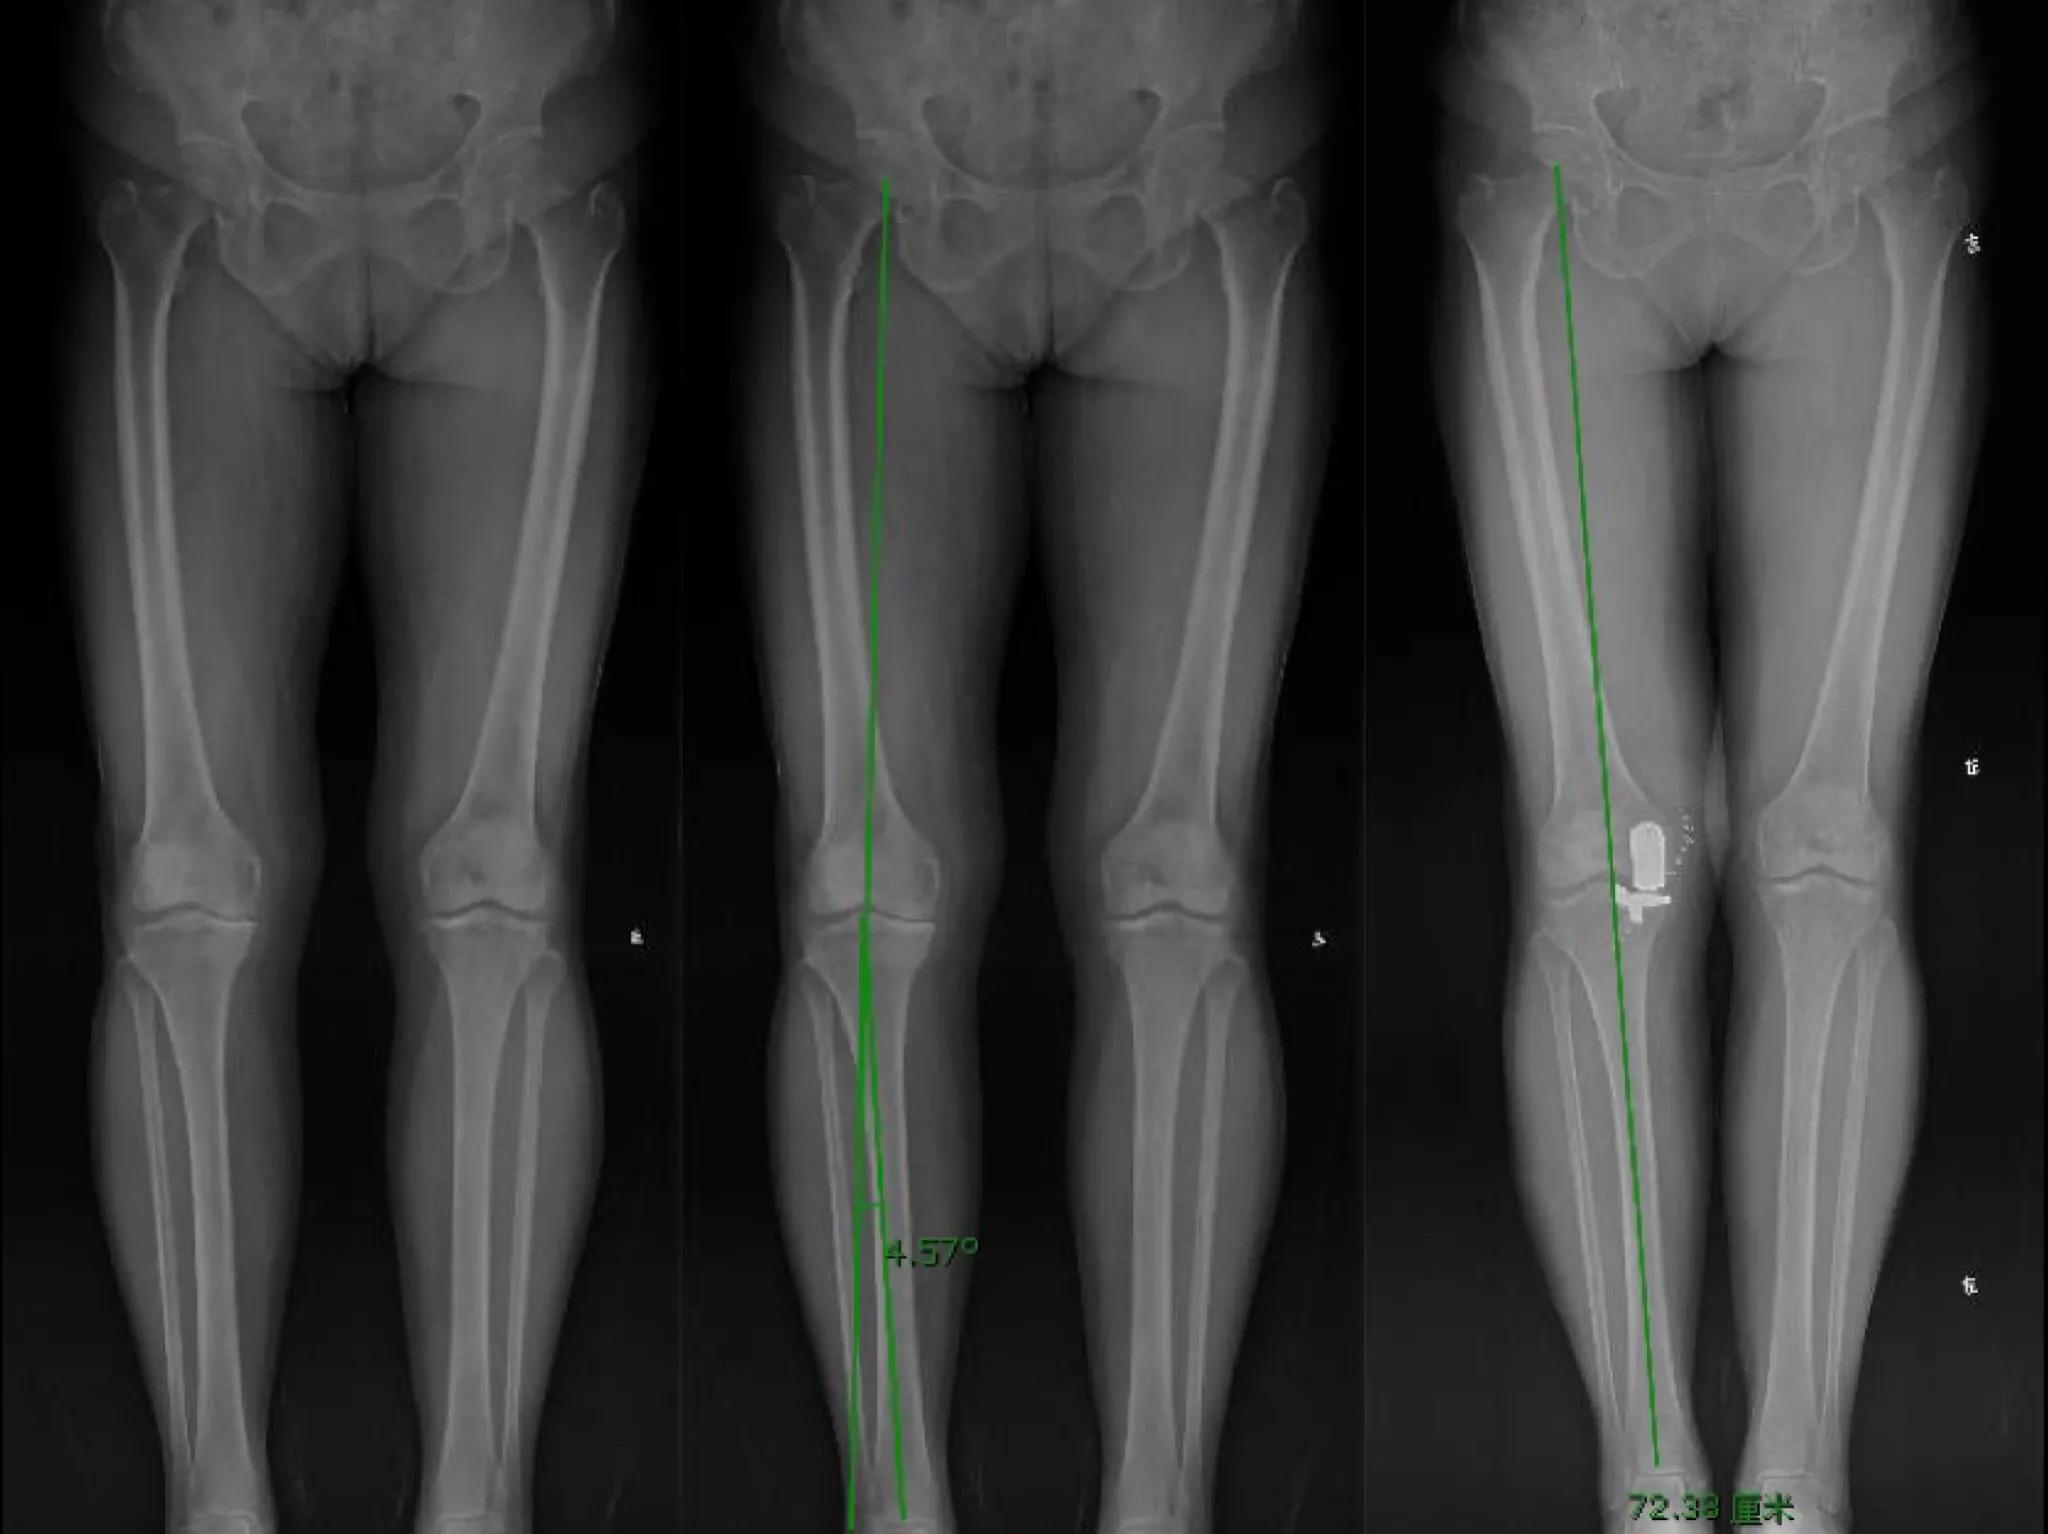

病例二:患者女性,73岁,右膝关节内侧负重时疼痛2年,加重4月余。查体:右膝关节轻度内翻,前内侧固定压痛点,膝关节ROM:伸10°—屈110°。双下肢全长负重位X线片示右膝关节内翻4.5°,关节间隙内侧明显狭窄。胫骨近端内侧角87°。

该患者年纪较长,膝关节活动轻度受限,胫骨内翻小于5°,胫骨近端内侧角正常,膝关节内翻为关节内软骨磨损所致,且可以通过外翻应力完全纠正,膝关节外侧间室功能正常。因此,本病例选择内侧单髁膝关节成形术(Unicompartmental Knee Arthroplasty, UKA)治疗,手术选择活动平台假体,恢复内侧副韧带长度和张力,纠正关节内翻畸形。术后双下肢全长负重位X线片示右下肢力线通过膝关节中心。